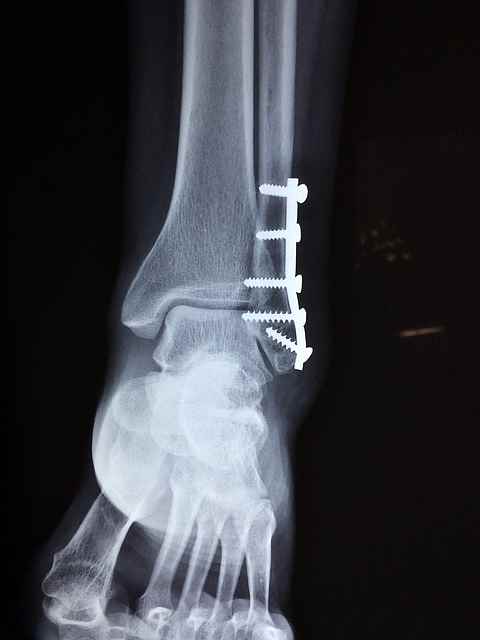

6. 외상이나 골절

골다공증의 특징적인 증상 중 하나는 외상이나 힘이 거의 없는 상태에서 골절의 위험이 증가한다는 것입니다. 허리를 굽히거나 기침을 하거나 심지어 가벼운 돌기가 있는 경우에도 골절이 발생할 수 있는데, 특히 엉덩이, 척추, 손목과 같은 체중이 많이 나가는 뼈에 골절이 발생할 수 있습니다. 큰 부상 없이 골절을 경험했다면, 향후 골절과 합병증을 예방하기 위해 의사와 함께 뼈 건강에 대한 근본적인 관심사를 조사하는 것이 필수적입니다.